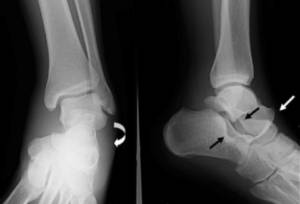

Снимки делаются в двух перпендикулярных проекциях. Определенные симптомы помогут врачу правильно определить тип травмы по изображениям. Для уточнения диагноза в соответствии с МКБ 10 после основного метода могут назначить также МРТ, КТ. Провести такую диагностику дома невозможно, поэтому в больницу нужно идти обязательно!

При подозрении на вывих голеностопа врач осматривает сустав. После приема доктор направит на обследование – рентгенографию, компьютерную томографию или магнитно-резонансную томографию. Это нужно, чтобы выяснить, есть ли повреждения костей, связок и насколько они сильные.